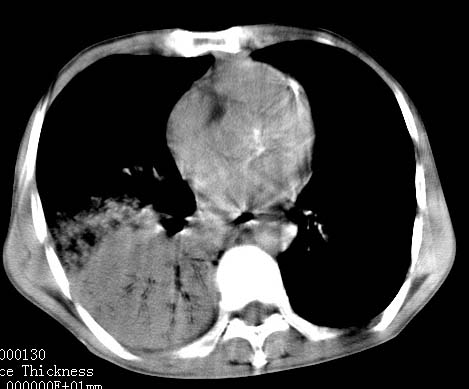

病人女 60岁 咳嗽 气促十余天,大叶性肺炎.

右肺上下叶均见 大片状密度增高影,边界清晰,其内可见支气管充气征,气管支气管通畅。纵膈略向右移位,其内无肿大淋巴结影。首先考虑炎性病变。不排除一些特异性的炎症。不知道发烧吗??wbc高吗??建议治疗后复查!!

看影响还是首先考虑炎性改变,建议实验室检查,还有要警惕炎性肺泡癌,具有的枯枝征象。

右肺感染性病变(大叶性肺炎可能);建议抗炎治疗后复查。

看影像还是首先考虑炎性改变,建议实验室检查,还有要警惕炎性肺泡癌,具有的枯枝征象